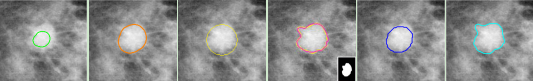

(a) (b) (c) (d) (e) (f)

图1. 不同高阶形状先验的实验对比。当分割对象呈现复杂形态特征时:(a)最小长度先验倾向于生成更小更平滑的区域;(b)凸性先验施加过强的凸形状约束;(c)TRIC强制严格的不切实际的圆形区域形状;(d)语义形状先验需要预定义的形状模板且计算成本高;(e)图紧凑性先验无法捕获关键的解剖区域细节;(f)本研究方法成功捕获全局区域形状和精细尺度细节!